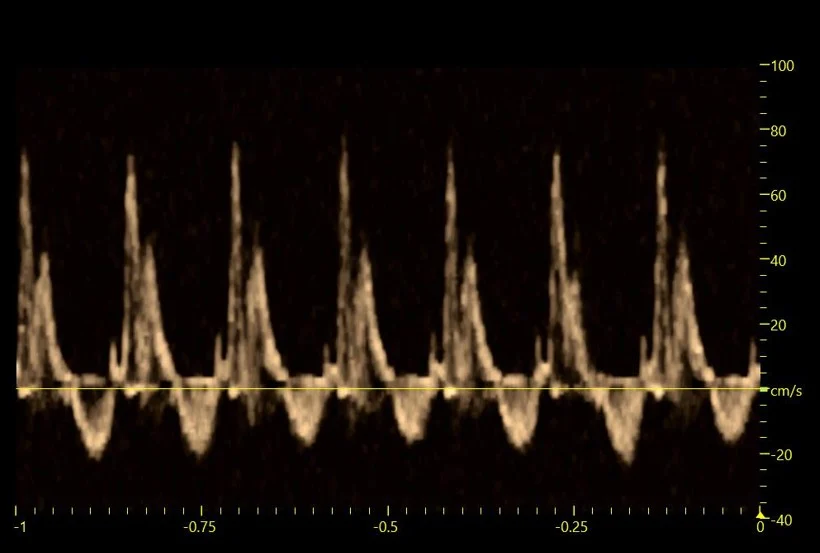

В исследованиях института эхокардиография выполняется с использованием допплеровских режимов. Классическая допплерография обеспечивает количественную оценку скорости и направления кровотока в сосудах и полостях сердца, а режимы тканевого допплера позволяют регистрировать скорость и особенности движения миокарда. Такое сочетание структурной визуализации и допплер‑оценки гемодинамики делает ЭхоКГ информативным инструментом для раннего выявления кардиотоксических эффектов и подтверждения кардиопротективного действия перспективных препаратов.